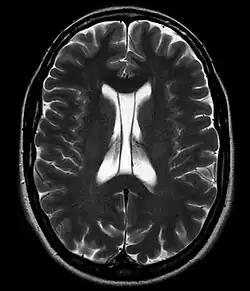

Полость прозрачной перегородки (лат. cavum septi pellucidi) — полость, находящаяся между листками прозрачной перегородки. Полость содержит ликвор, попадающий туда через поры в листках.[1]

Спереди полость ограничена коленом мозолистого тела; сверху — стволом мозолистого тела; сзади — передними ножками и столбами свода мозга; снизу — передней комиссурой и клювом мозолистого тела; латерально — листками прозрачной перегородки.[2]

Размер полости крайне вариабелен, у некоторых полость полностью закрыта, в то время как у других отмечается практически полное её незаращение (до 46 мм в корональной плоскости).[3]

В большинстве случаев полость не сообщается с полостью желудочковой системы мозга, что делает неправомочным её описание как «5-го желудочка» головного мозга, тем не менее, иногда её называют пятым желудочком.

Собственно полость прозрачной перегородки расположена на уровне основания передних рогов боковых желудочков мозга, а её распространение в заднем направлении в область тел боковых желудочков выделяют под названием полость Верге (лат. cavum vergae). Во время эмбрионального развития происходит закрытие полостей в задне-переднем направлении, из-за чего персистирование полости Верге при закрытой полости прозрачной перегородки встречается значительно реже.